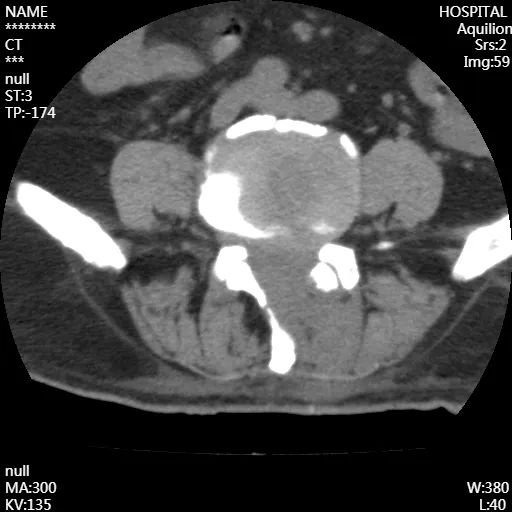

術(shù)后

腰椎CT成像

從影像上看出,患者術(shù)后神經(jīng)壓迫情況得到了改善